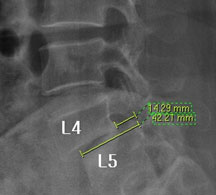

즉, 척추전방위증은 통증을 일으키는 원인질환(디스크, 협착증)을 치료하는 것이 척추 뼈를 더 이상 앞으로 밀려나가지 않게 하는 치료라고 볼 수 있습니다. 모커리는 뼈가 50% 이상 밀려나간 2단계의 척추전방위증도 비수술로 치료하고 있으며, 이러한 한방치료 효과를 객관적으로 검증하여 유명학회 및 논문에 계속해서 발표하고 있습니다.

모커리한방병원은 50% 정도 밀려나간 2단계의 척추전방위증 환자를 대상으로 약 3주간의 입원집중치료를 실시한 결과, 입원 시보다 80% 이상 통증이 감소되어 치료되었습니다. 통증 없이 걷는 시간도 약 3배 정도 증가되어 단기간에 수술 없이 높은 치료효과가 나타났다는 것을 대한침구의학회에 발표하였습니다. 50% 정도 밀려나간 2단계의 중증 척추전방전위증 환자이면서 심한 척추협착증 증상을 나타내는 환자를 치료한 결과입니다.